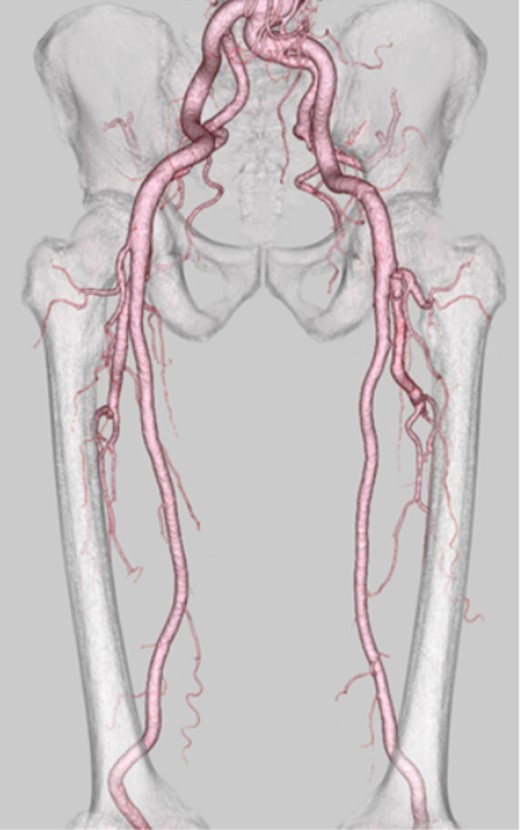

A 58-year-old man presented with paralysis and pain in the left leg, and a mass was found in his thigh. Because of the growth of the mass and the worsening of his symptoms, the patient visited a neighboring hospital. Computed tomography confirmed the presence of a femoral arterial aneurysm. He visited our hospital for more detailed examinations and medical treatment. Physical examination revealed a pulsatile mass with a diameter of 8 cm in the left thigh. The patient had no history of trauma, previous operations or interventions. He had medication-controlled hypertension. Multidetector computed tomography performed in our hospital revealed a large DFA aneurysm with an intraluminal thrombus (Fig. 1). An image diagnosis of a DFA aneurysm was made. There was no evidence of aneurysms or occlusive lesions in the other arteries. Surgical intervention was planned because of the large size of the aneurysm, the high risk of perforation and the worsening symptoms.

Multidetector computed tomography revealed a large DFA aneurysm (arrows show aneurysm).